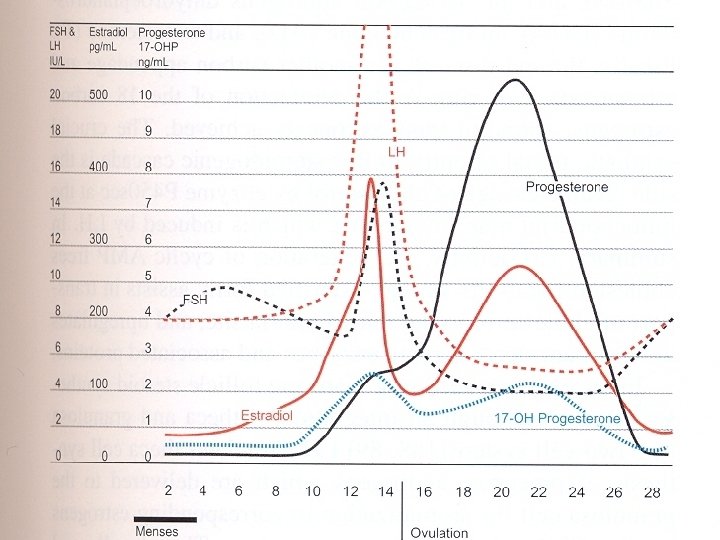

Follicular Maturation FSH • Induces early growth • Controls follicle number LH • Provides estrogen precursors • Needed for latter stages of growth

Erken Foliküler Faz Thecal cell LH Androstenedione Testosterone Granulosa cell FSH IGF II Aromatisation E 1 E 2

Follicle-stimulating Hormone (FSH ) • • FSH hormone is secreted by anterior pituitary Turned on by Gn. RH Negative feedback inhibition with estrogen Causes maturation of dominant ovarian follicle

Luteinizing Hormone (LH) • • Secreted by anterior pituitary Turned on by estrogen Maintains corpus luteum Causes corpus luteum to secrete progesterone

Positive feed back of E 2 more than 200 pg /ml > 50 hours

A threshold of LH 14 -27 hours for full maturation of the oocyte to occur